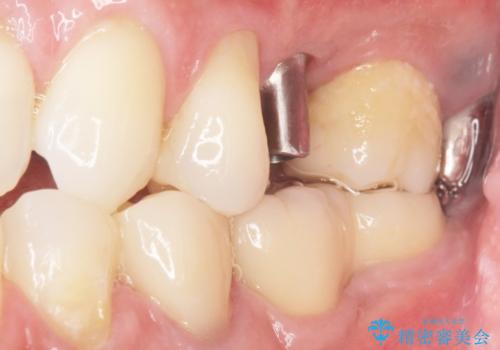

骨の厚みが不足していたため、インプラントの埋入と同時にソケットリフト(上顎骨に骨を増やす手術)を行いました。

インプラントの種類:ストローマン BLT

被せ物の種類:オールセラミッククラウン スタンダード